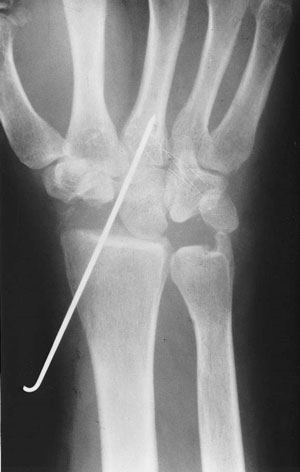

Las técnicas de descompresión consisten en realizar osteotomías de acortamiento (cortar hueso) del radio o del hueso grande, con el objetivo de disminuir la sobrecarga del semilunar.

Nosotros realizamos una osteotomía de valguización del radio que consiste en extraer una cuña de base radial y se fija con una placa (figura 9).

El tratamiento quirúrgico varía dependiendo del estadio radiológico y de la demanda funcional del paciente. En los estadios I, II, IIIA se realizan medidas de descompresión y revascularización, en el IIIB técnicas de descompresión o paliativas y en el IV solo medidas paliativas.

Figura 9